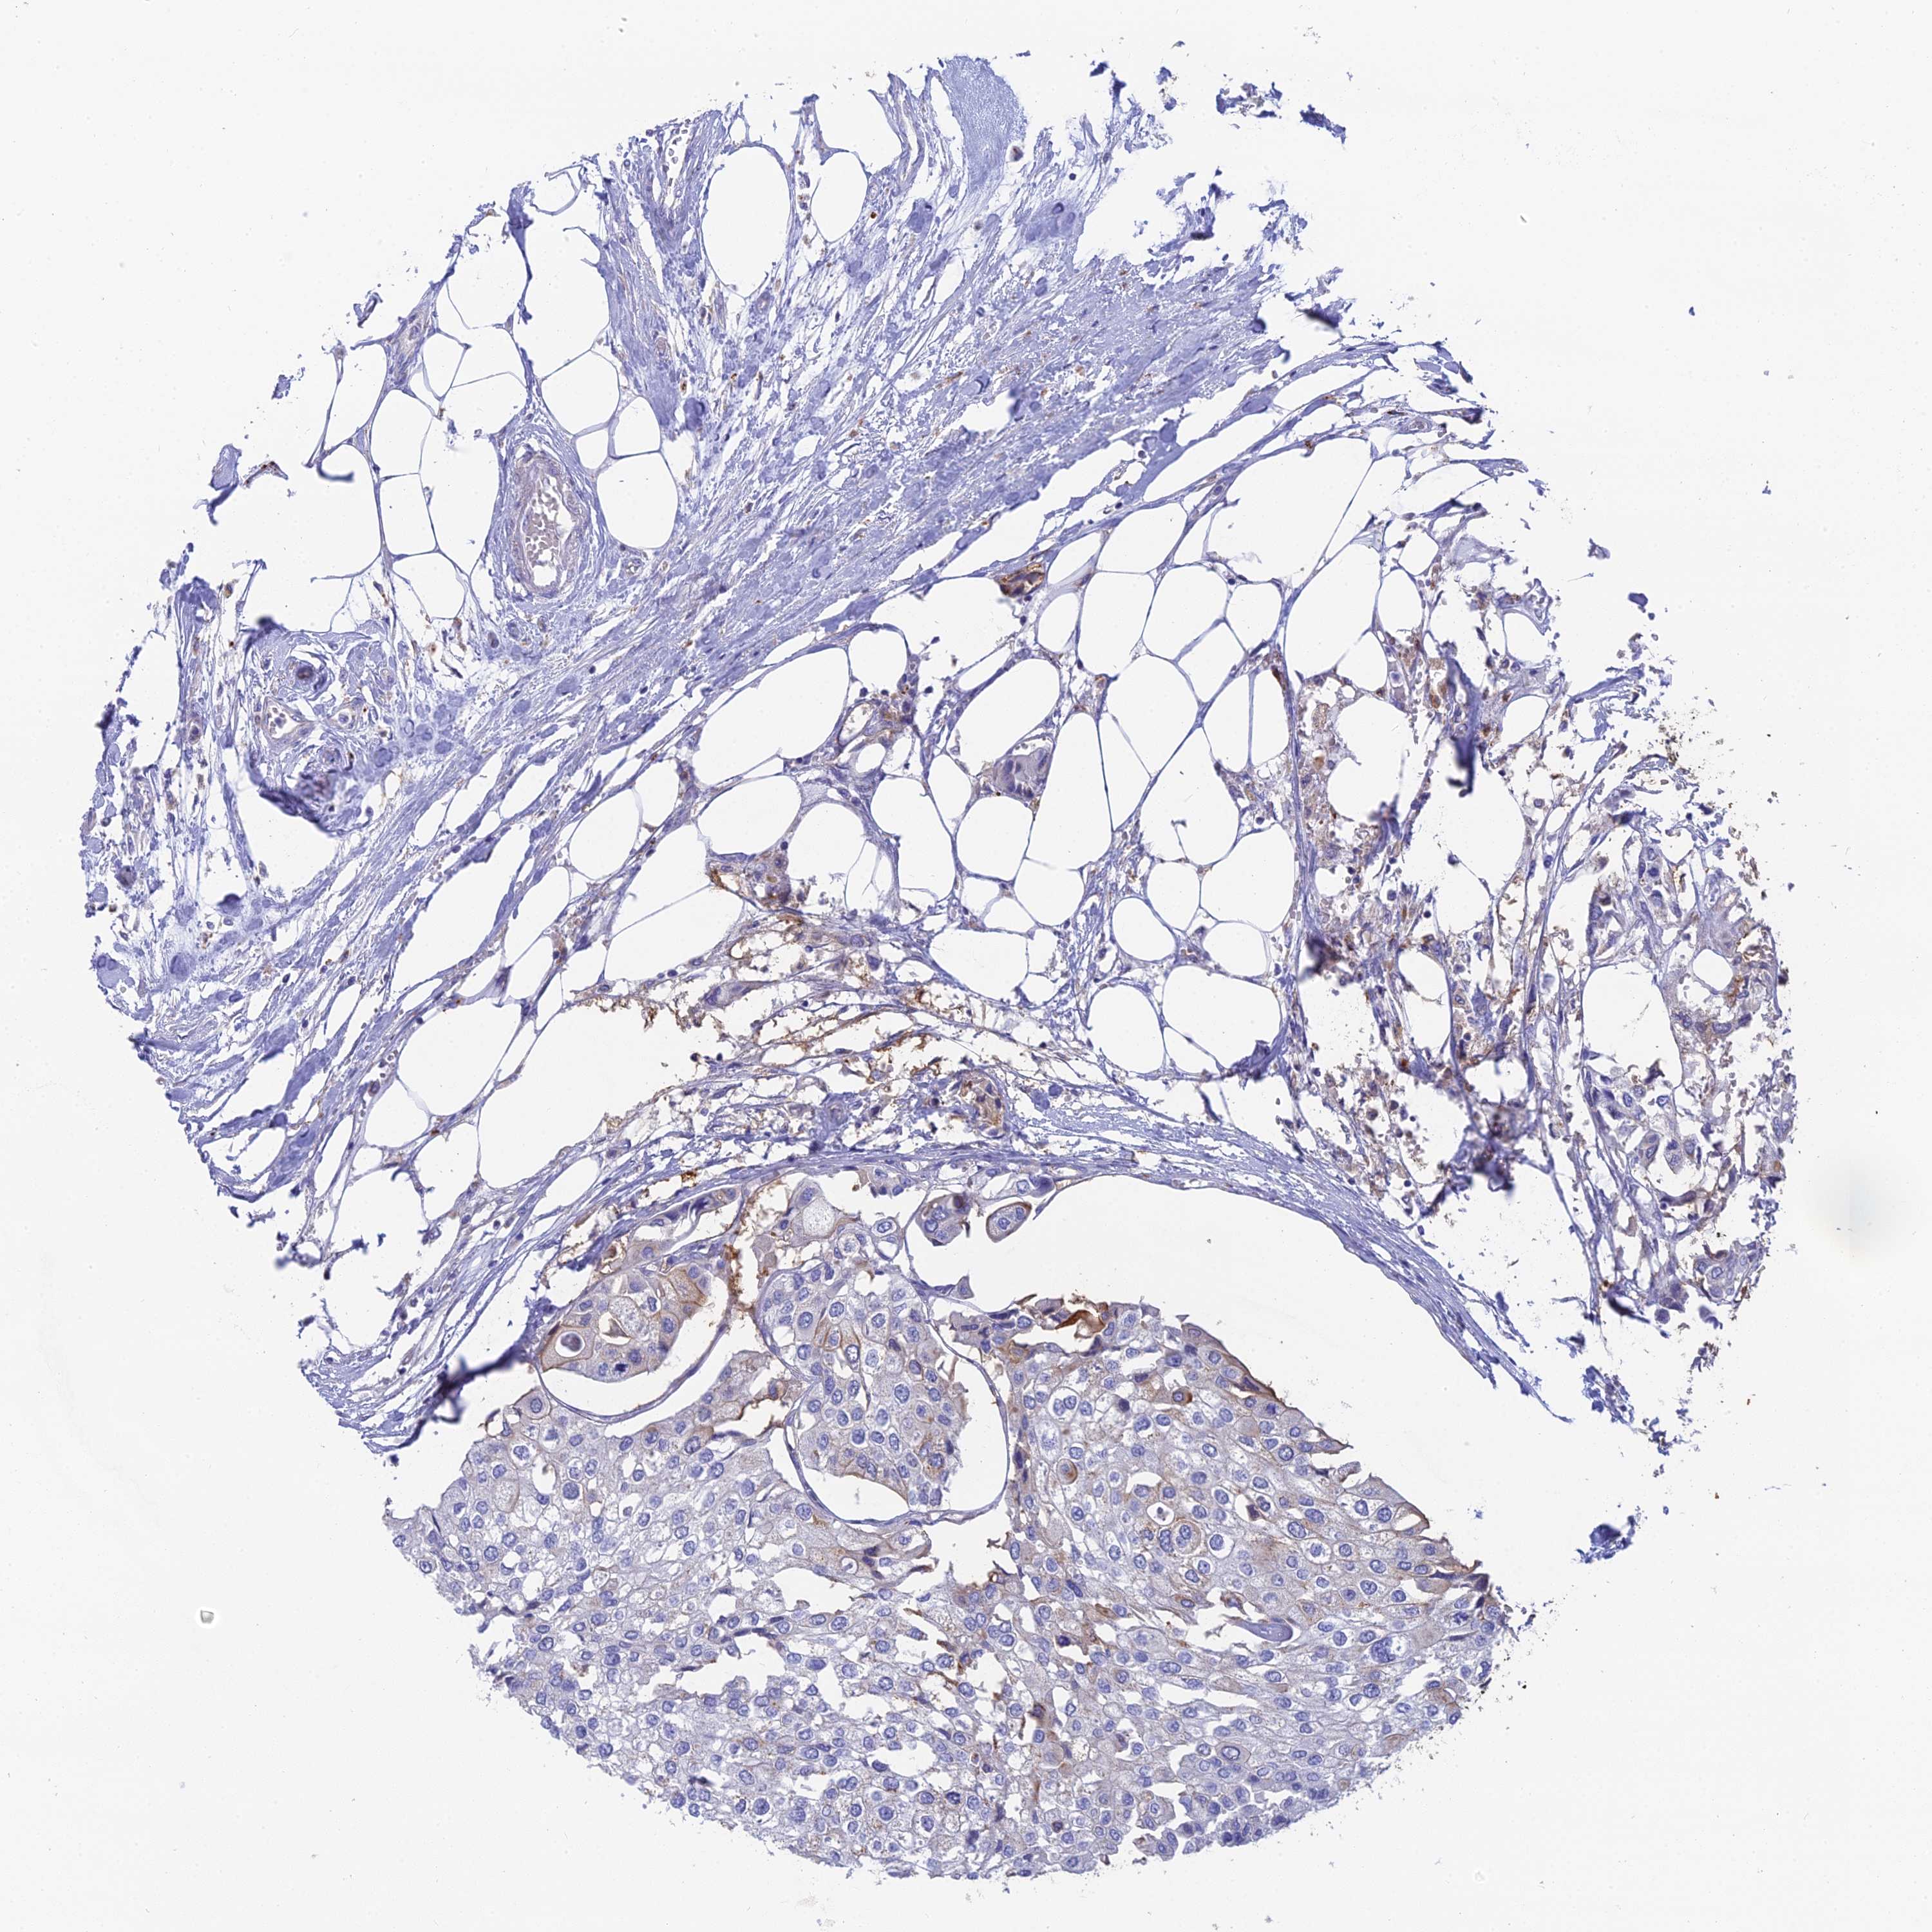

UROTHELIAL CANCER - Protein expressioni

A mouse-over function shows sample information and annotation data. Click on an image to view it in a full screen mode. Samples can be filtered based on level of antibody staining by selecting one or several of the following categories: high, medium, low and not detected. The assay and annotation is described here.

Note that samples used for immunohistochemistry by the Human Protein Atlas do not correspond to samples in the TCGA dataset.

Antibody stainingi

Antibody staining in the annotated cell types in the current human tissue is reported as not detected, low, medium, or high, based on conventional immunohistochemistry profiling in selected tissues. This score is based on the combination of the staining intensity and fraction of stained cells.

Each image is clickable and will lead to virtual microscopy that enables deeper exploration of all samples and also displays staining intensity scores, fraction scores and subcellular localization as well as patient and tissue information for each sample.

Antibody HPA042622

Staining

High

Medium

Low

Not detected

Intensity

Strong

Moderate

Weak

Negative

Quantity

>75%

75%-25%

<25%

None

Location

Urothelial carcinoma, High grade

Urothelial carcinoma, Low grade